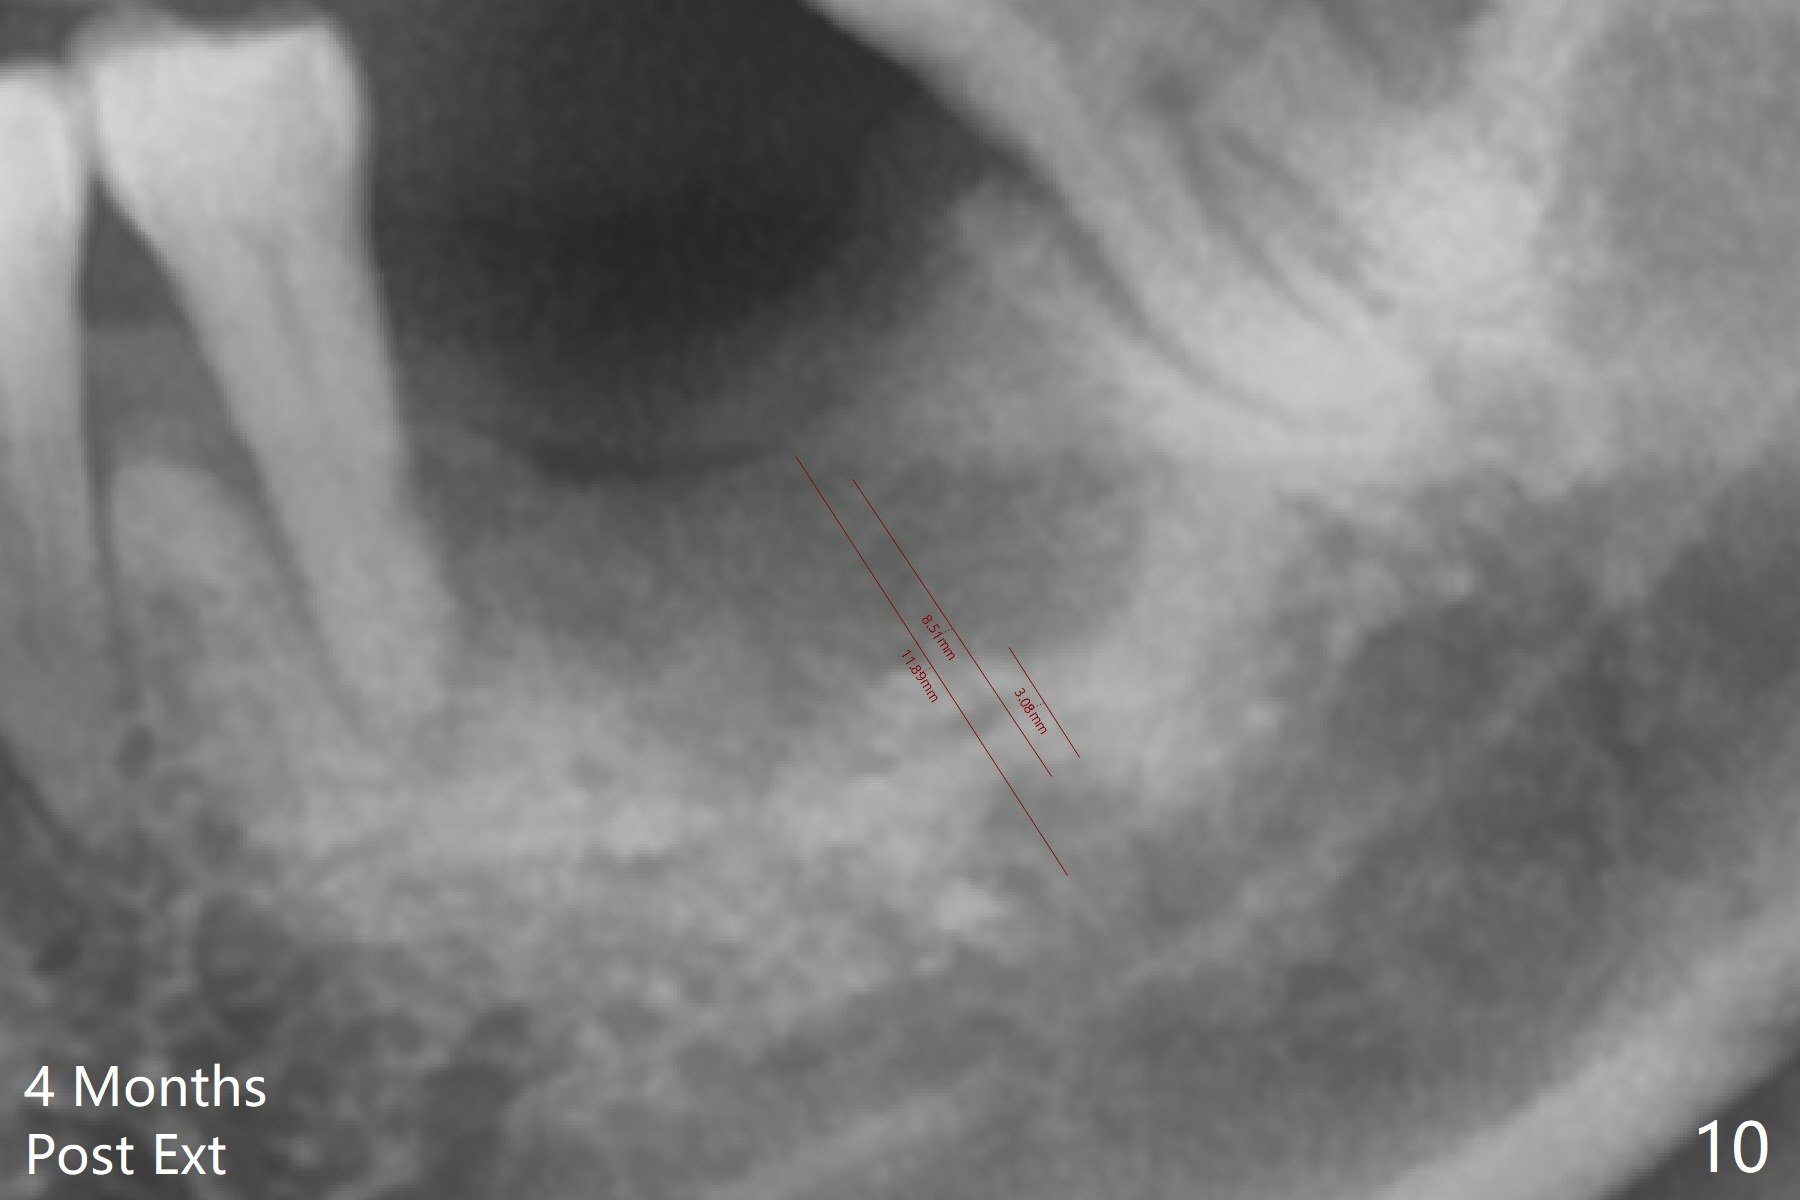

A 63-year-old man is a diabetic with history of good control. He masticates unilaterally with missing teeth #2,3 and 24 (Fig.1 (taken 5 years ago)). The latter has been restored with an implant. Last February the mesial root of the tooth #19 was found to have vertical fracture with bone loss until the base of the septum (Fig.2). The bone available for implantation is ~7-8 mm after root fracture (Fig.3,4). The initial osteotomy depth will be 7 mm (IS kit), followed by the calibrated parallel pin. The latter determines how many millimeters of an implant will be surrounded by the graft bone (Fig.4,5 (green: implant length; pink: cuff; blue: abutment length)). Since the buccal defect is severe with mesial root split (Fig.7 *), draw blood for PRF (2 large tubes). To save the remaining septum, place 2 of 1-piece implants on the either side of the septum (compare Fig.6,8). Take photos to compare buccal vs. lingual gingival recession. Tell the patient that the tooth #20 may be nonsalvageable. Since insurance preauthorization does not get approval for several times, the tooth #19 is extracted with socket preservation and periodontal dressing. The latter dislodges in 1 day. When the patient returns for follow up 4 days postop, the socket is exposed (Fig.9). An immediate implant should have been placed to keep the graft in place. PRF also helps. In fact preauthorization letter arrived 1 day earlier. It appears that guided surgery is indicated for limited bone height. The bone graft appears to gain ~ 5 mm bone in 4 months (Fig.10), which allows to place a 5x8.5 mm implant (Fig.11).